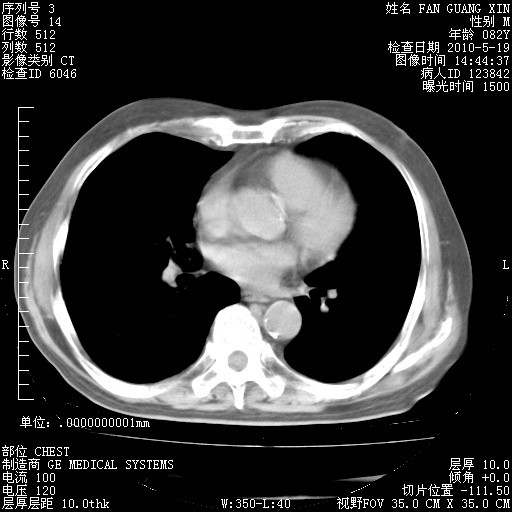

可改为口服强的松40-50mg/d治疗,若病情仍稳定,胸部阴影不再吸收可逐渐减量